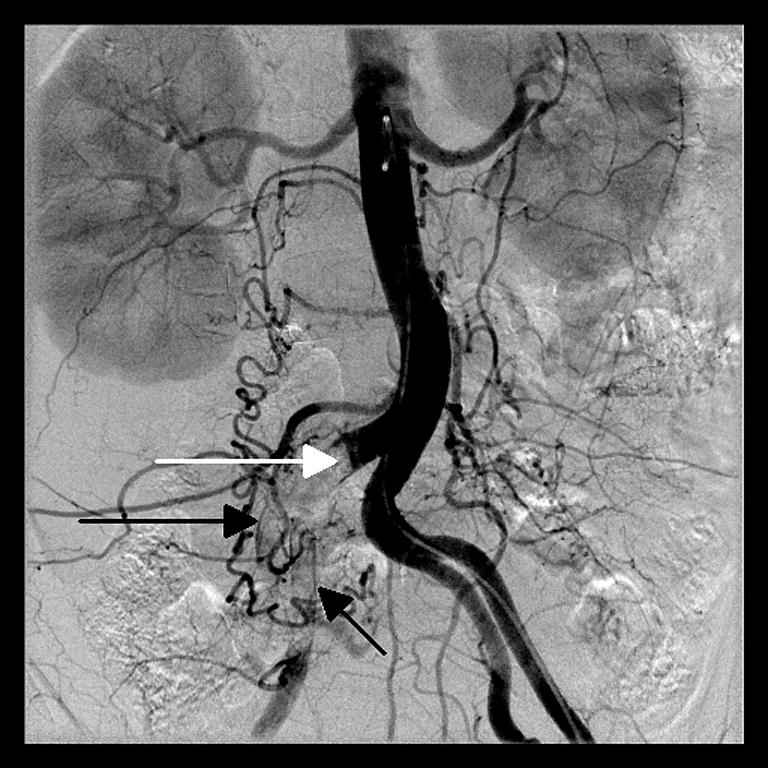

In arteriogram, there were filling defects at the distal part of the right common iliac artery, and at the internal and external iliac arteries, whereas the appearance of the arteries were normal at the left side. The arteriogram also showed poor filling of the right superficial femoral and popliteal arteries (Fig. 1). However, there were filling defects at the tibioperoneal trunk, proximal part of the peroneal artery and anterior tibial artery (Fig. 2a and b). The posterior tibial artery was patent, and the poor filling of the peroneal artery was observed. However, there were no flow at the right crural arteries and the left anterior tibial artery except the proximal part of the left anterior tibial artery (Fig. 3a and b).

In arteriogram, there were filling defects at the distal part of the right common iliac artery (white arrow), and internal (short black arrow) and external (long black arrow) iliac arteries, whereas the appearance of the arteries were normal at the left side.